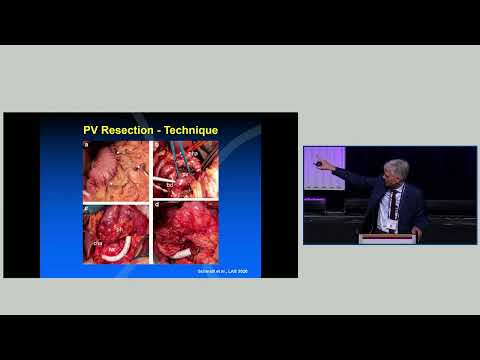

DEB01: Open vs Robotic; PDAC with Vascular Involvement

Debate 01: Open vs Robotic; PDAC with Vascular Involvement